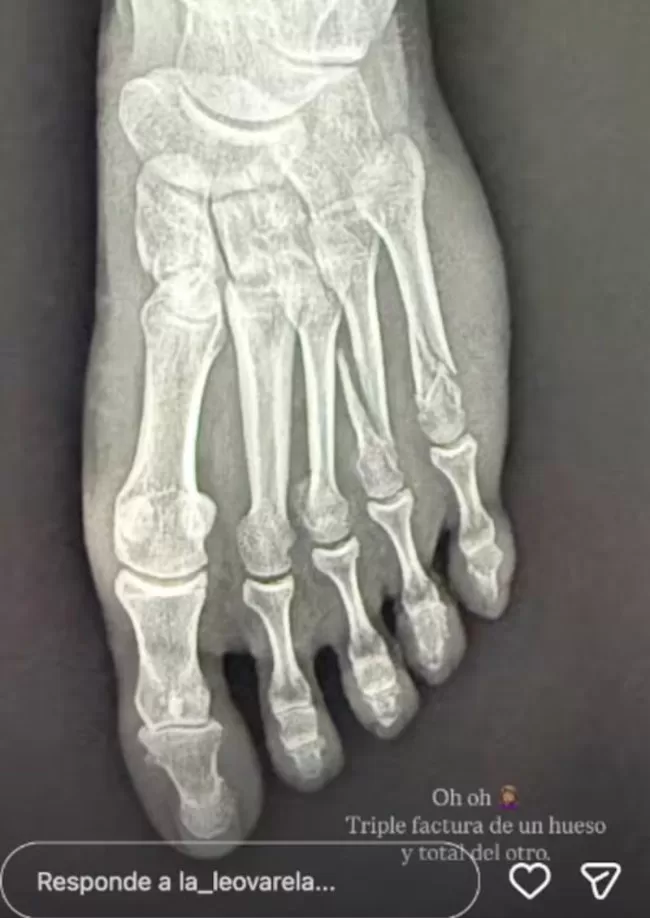

Leonor Varela compartió una imagen de una radiografía de su pie lastimado. En este sentido señaló: «Oh, oh. Triple fractura de un hueso y total del otro».